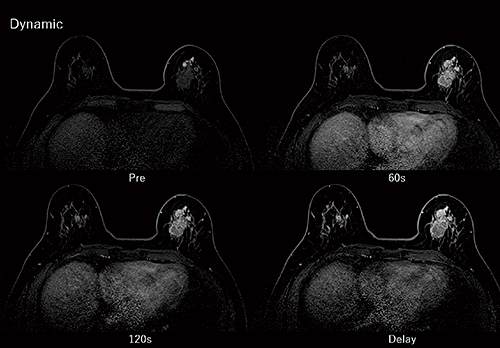

図2 乳房画像(浸潤性乳管癌)

脂肪抑制法Enhanced Fat Freeを用いることにより、両側均一の脂肪制画像が得られている。